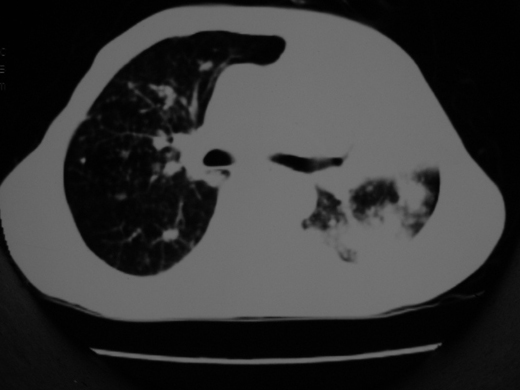

男69岁,年前胸片示肺感染治疗近一月今复查无明显好转,血象正常

双肺内不规则斑点状 片状及结节密实影,部分灶周见索条样影及\"树芽征\",左肺上叶实变,内见充气支气管影及斑状钙化,左侧少量胸腔积液,考虑1)双肺结核2)左侧胸腔积液

右肺多发片絮状结节状及时条索状影,左上肺实变,内可见虫蚀样空洞及支气管气象,左下肺片状及球形病灶,及胸腔积液征象,双肺病灶内多发钙化影,结合病史,考虑双肺继发型肺结核,左胸腔积液

右肺多发片絮状结节状及时条索状影,左上肺实变,内可见虫蚀样空洞及支气管气象,左下肺片状及球形病灶,及胸腔积液征象,双肺病灶内多发钙化影,上纵隔向左侧移位,结合病史,考虑双肺继发型肺结核,左胸腔积液。

右肺多发片絮状、结节状及条索状影,左上肺实变,内可见虫蚀样空洞及支气管气象,左下肺片状及球形病灶,有胸腔积液征象,双肺病灶内多发钙化影,上纵隔向左侧移位,结合病史,考虑双肺继发型肺结核,左胸腔积液。 建议结合ppd检查或纤支镜检查!

双肺结核,左肺实变。左侧胸腔积液(部分包裹)。